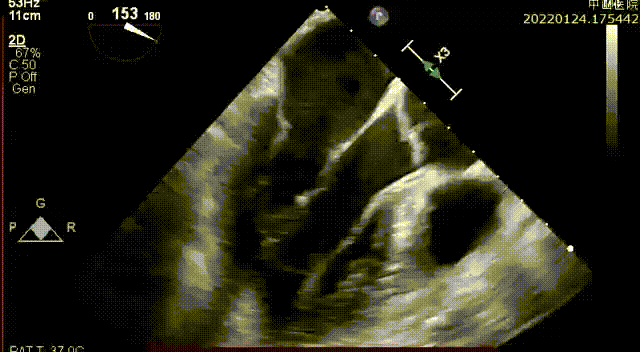

术前重度反流

患者全麻后,在左胸心尖对应处胸壁切开4cm微小切口,随即在经食道超声引导下,使用E-Chord®二尖瓣修复装置在P2-P3区域成功植入三对人工腱索并固定在心尖,二尖瓣反流立刻完全消失。手术全程约1小时,其中心内操作时间仅20分钟,可谓行云流水、一气呵成。手术无需体外循环、无需心脏停跳、无需心脏切开,E-Chord®系统直径只有 3mm(9F),是全球最细的二尖瓣修复装置,创伤极小,几乎无出血。手术在完全超声引导下进行,不但定位精确,且无任何放射线,堪称“绿色介入手术”。